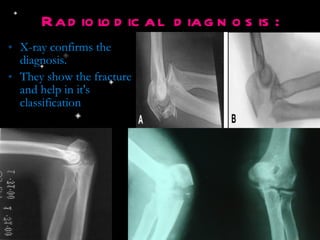

Radiolodical diagnosis: X-ray confirms the diagnosis. They show the fracture and help in it's classification

Radiolodical diagnosis: X-rayconfirms the diagnosis. They show the fracture and help in it's classification